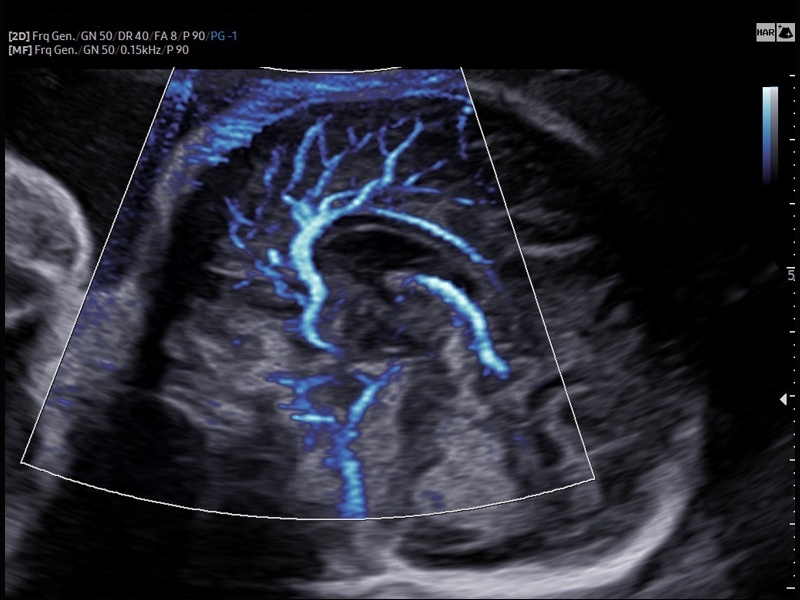

• Расширенная сосудистая визуализация: Auto IMT+, 2D Arterial Analysis

• Технологии визуализации: MV Flow, LumiFlow, SEE Stream, Panoramic

• Модуль AutoIMT - автоматическое вычисление комплекса интима-медиа общей сонной артерии (Intima Media Thickness). Данная оценка имеет большое значение для ранней диагностики атеросклероза и оценки риска развития инсульта и инфаркта миокарда.

• Модуль MV-Flow – программа (режим), позволяющая визуализировать кровоток в микроциркуляторном русле с высоким разрешением без использования контраста.

• Модуль LumiFlow – программа отображения кровотока с объемной графикой для лучшего понимания архитектоники сосудистого русла.

• Модуль 2D Arterial Analysis программа, позволяющая автоматически провести анализ толщины и эластичности стенок разных участков сонной артерии, с выведением результатов в графической форме в движении (кинопетле) аналогично программе Strain для эхокардиографии.